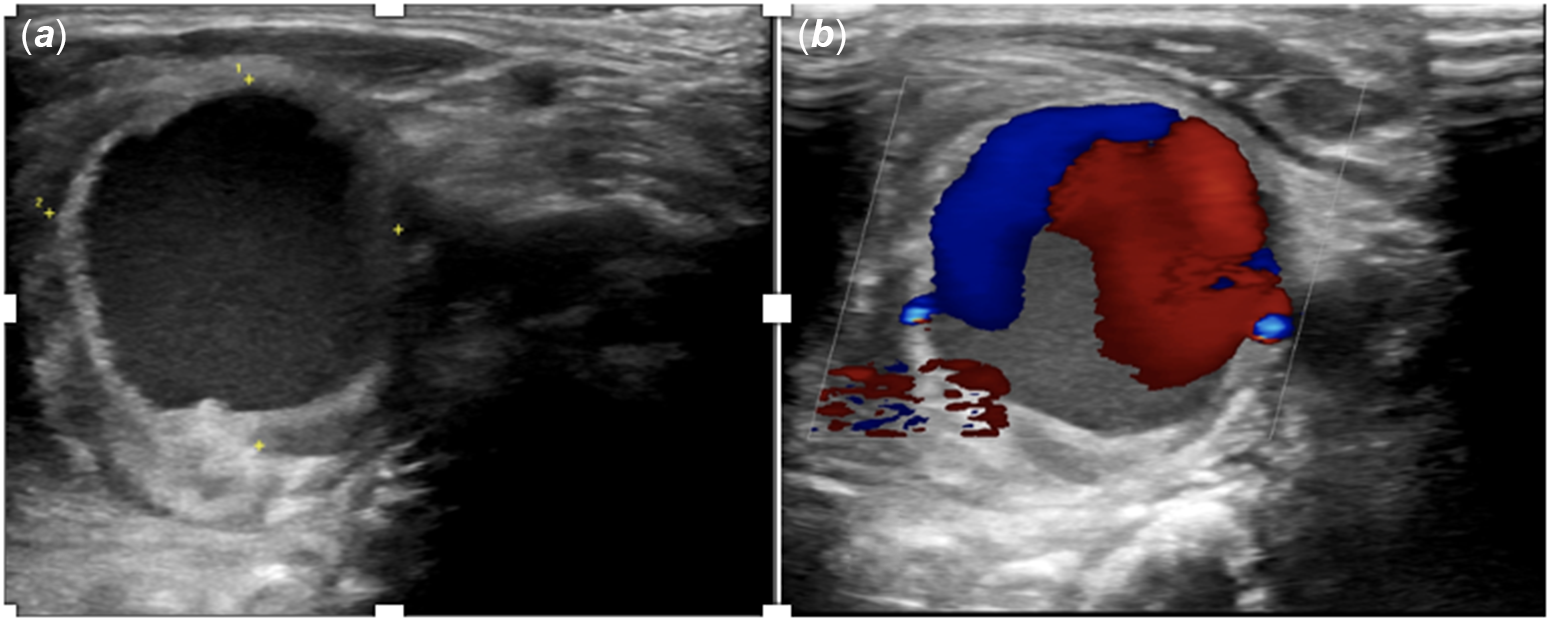

A 6-month-old girl was admitted to the hospital for evaluation for coarctation balloon angioplasty. In medical history, the patient was operated on due to aortopulmonary window, interrupted aortic arch, and aortic coarctation when she was 12 days old. Balloon angioplasty was performed for recoarctation 1 month later. Then, she underwent a second operation due to left phrenic nerve palsy. The patient was referred for evaluation due to recoarctation. On physical examination, she weighed 4.3 kg and revealed scars from previous surgeries around the left thoracotomy and left subcostal region. The femoral pulses were weak. A 2/6 systolic ejection murmur was heard in the interscapular region. On the echocardiogram, there were left ventricular hypertrophy and diastolic flow pattern in descending aorta. It was decided to perform a balloon coarctation angioplasty for the recurrence of the aortic coarctation. In the catheter laboratory, efforts to find access from femoral and axillary arteries were unsuccessful. Left common carotid artery access was performed by using an 18-gauge needle and 0.035-inch wire under ultrasound guidance, and a 4F sheath was inserted. Intravenous heparin 30 unit per kilogram was admitted. There were no complications during the procedure (Fig 1). The patient was discharged from the hospital one day after the procedure. After 10 days, the family noticed a prominent mass on the left side of the patient’s neck. The patient was called in for control. During the patient’s examination, a 2 × 2 cm pulsating mass on the left side of the neck, with no signs of infection on the skin, was noted (Fig 2). On ultrasound, a 2 × 2 cm pseudoaneurysm was detected adjacent to the left common carotid artery (Fig 3). To better assess the location. of the pseudoaneurysm, a CT angiography was performed. CT revealed a 3 × 3 cm pseudoaneurysm with a 3 mm connection with the left common carotid artery, located 2 cm below the bifurcation. Due to the pseudoaneurysm, the trachea and surrounding structures were noted to be shifted to the right side (Fig 4). The management was discussed with the department of interventional radiology. A stent graft was not suitable since the patient was an infant. Even the pseudoaneurysm neck was narrow, percutaneous thrombin injection still had a risk of distal emboli, and it was not possible to insert a filter into common carotid artery due to unattainable femoral access. With the department of cardiovascular surgery, it was decided upon to move forward with a surgical treatment plan. During the operation, considering the pseudoaneurysm sac’s growth direction, an incision was made lateral to the right sternocleidomastoid muscle. Sternocleidomastoid was excluded laterally, and the sac was partially exposed with a meticulous dissection. Proximal and distal parts of the carotid artery were identified and clamped after heparinisation. The pseudoaneurysm sac was excised, and the coagulum was removed. 1–2 mm needle hole on carotid artery was localised and closed with separated stitches (Fig 5). The clamps were removed, and the blood flow was re-established. The patient was extubated in the operating room and transferred to the paediatric ICU without any complications. The repeat ultrasound on the post-operative fourth day was normal, and the patient was discharged without any neurologic problems.

Figure 3. Carotid Doppler ultrasound revealed a 20 x 20 mm pseudoaneurysm in the left common carotid artery (A). "Yin Yang" colour pattern is specific for the pseudoaneurysm (B).